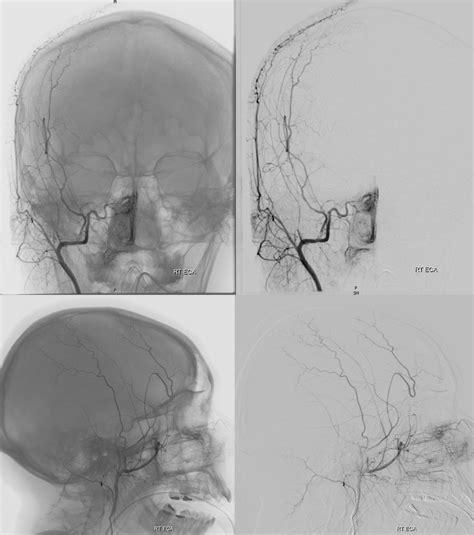

Diagnosing a Carotid Cavernous Fistula requires specialized imaging techniques to confirm the abnormal connection between the arteries and the venous sinus. Initial screenings often include:

• Digital Subtraction Angiography (DSA): Considered the “gold standard” for diagnosis, this invasive procedure allows physicians to see the exact site of the fistula and plan for endovascular intervention.

The goal of treating a Carotid Cavernous Fistula is to close the fistula while preserving the flow of blood through the internal carotid artery. In many cases, endovascular surgery is the preferred approach. During this minimally invasive procedure, a surgeon navigates a microcatheter through the blood vessels to the site of the fistula.